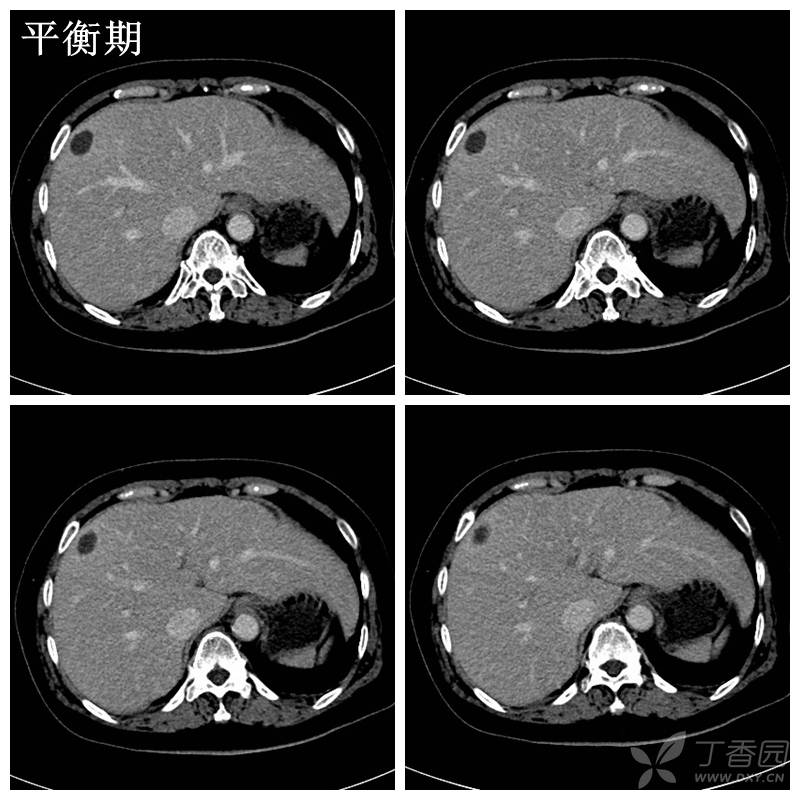

肝脓肿ct表现特点

典型肝脓肿平扫增强

图片尺寸512x512